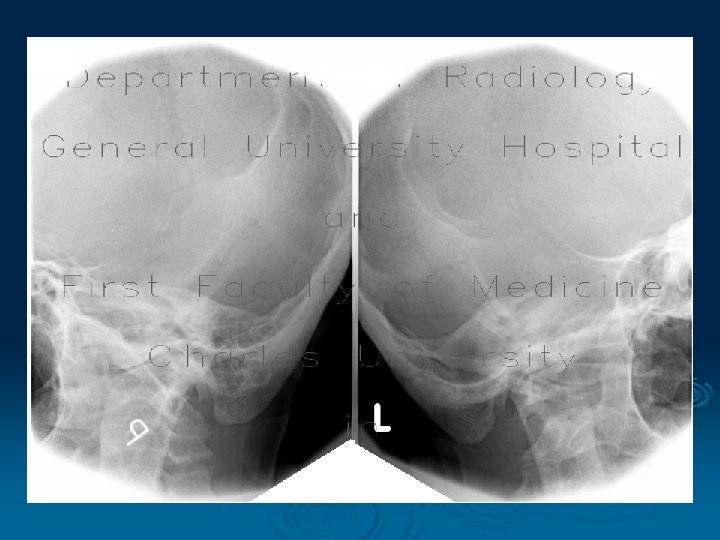

Schuller's Projection § Position with the head turned laterally on the side to be examined § The X-ray tube is angled craniocaudally (about 25°); the central X-ray exits the external auditory canal to be examined view with the mouth closed and opened allows appreciation of the temporomandibular joint dynamics

Albers-Schonberg View Lateral transfacial position - demostrated in open and closed positions (both sides are examined for comparison)